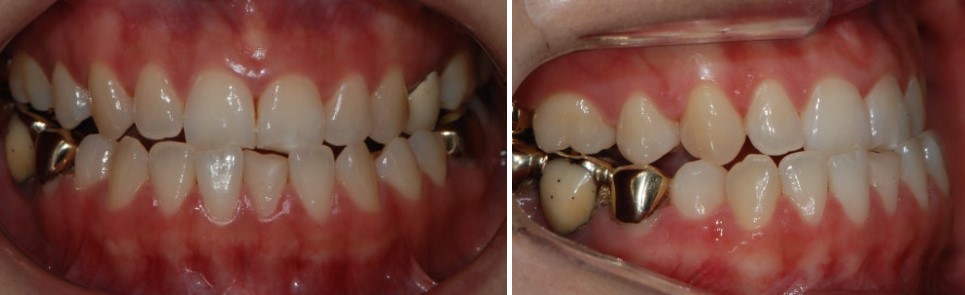

이 과정을 통해

앞니와 어금니 모두에서 매우 안정적인 교합이 형성되었고,

환자분이 원하셨던 기능적인 개선이 잘 이루어졌습니다.

그렇다면 옆모습은 어떻게 변했을까요?

치료 전·후 옆모습 X-ray를 비교해 보면,

수술을 하지 않았음에도 턱과 입 주변의 라인이 부드럽게 개선된 것을 확인할 수 있습니다.

케이스 2. 아래턱 돌출과 비대칭, 비수술 교정으로 가능한 만큼

두 번째 케이스는

아래턱이 앞으로 나와 있으면서 비대칭까지 동반된 경우였습니다.

치료 전 입안 사진과 X-ray를 보면,

교합이 전반적으로 매우 불안정한 상태였고,

옆모습에서도 턱 라인이 거칠게 느껴지는 케이스였습니다.